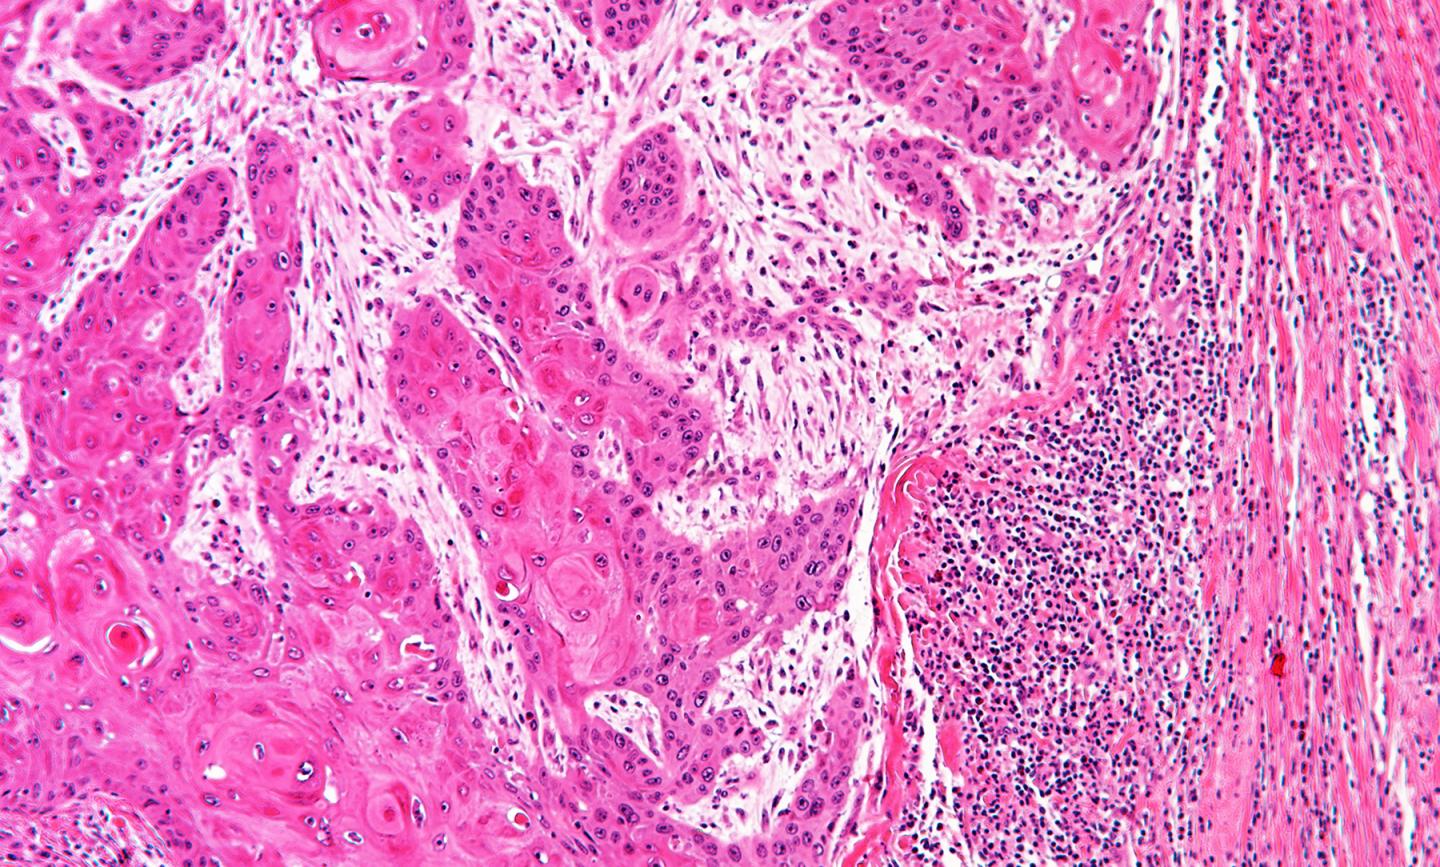

image: Human cancer under a microscope. The black dots on the right of the image are lymphocytes which are trying to get at the tumor, but are being stopped by cancer-associated fibroblasts. view more

Credit: University of Southampton

Immunotherapy treatment harnesses the power of the body's own immune system to fight cancer. Its success depends on 'killer' lymphocytes penetrating into a tumour to combat malignant cells. However, most patients fail to respond, often because the lymphocytes are blocked at the edge of the tumour, preventing their attack. The scientists behind this latest study believe they have found why this happens and identified a way to overcome it - potentially improving immunotherapy treatment for many patients with different types of cancer.

The team found that normal cells called cancer-associated fibroblasts (CAF) are hijacked by cancer cells to protect them from immune attack. Fibroblasts are healthy cells that normally maintain the structure of tissues, but when they are corrupted by cancer cells, they become CAFs and shield tumours from lymphocyte attack and stop immunotherapy from working effectively. A significant proportion of many solid cancers are CAF-rich and associated with poor survival, including more than 50 percent of cases of head and neck, esophageal, colorectal and pancreatic cancers.